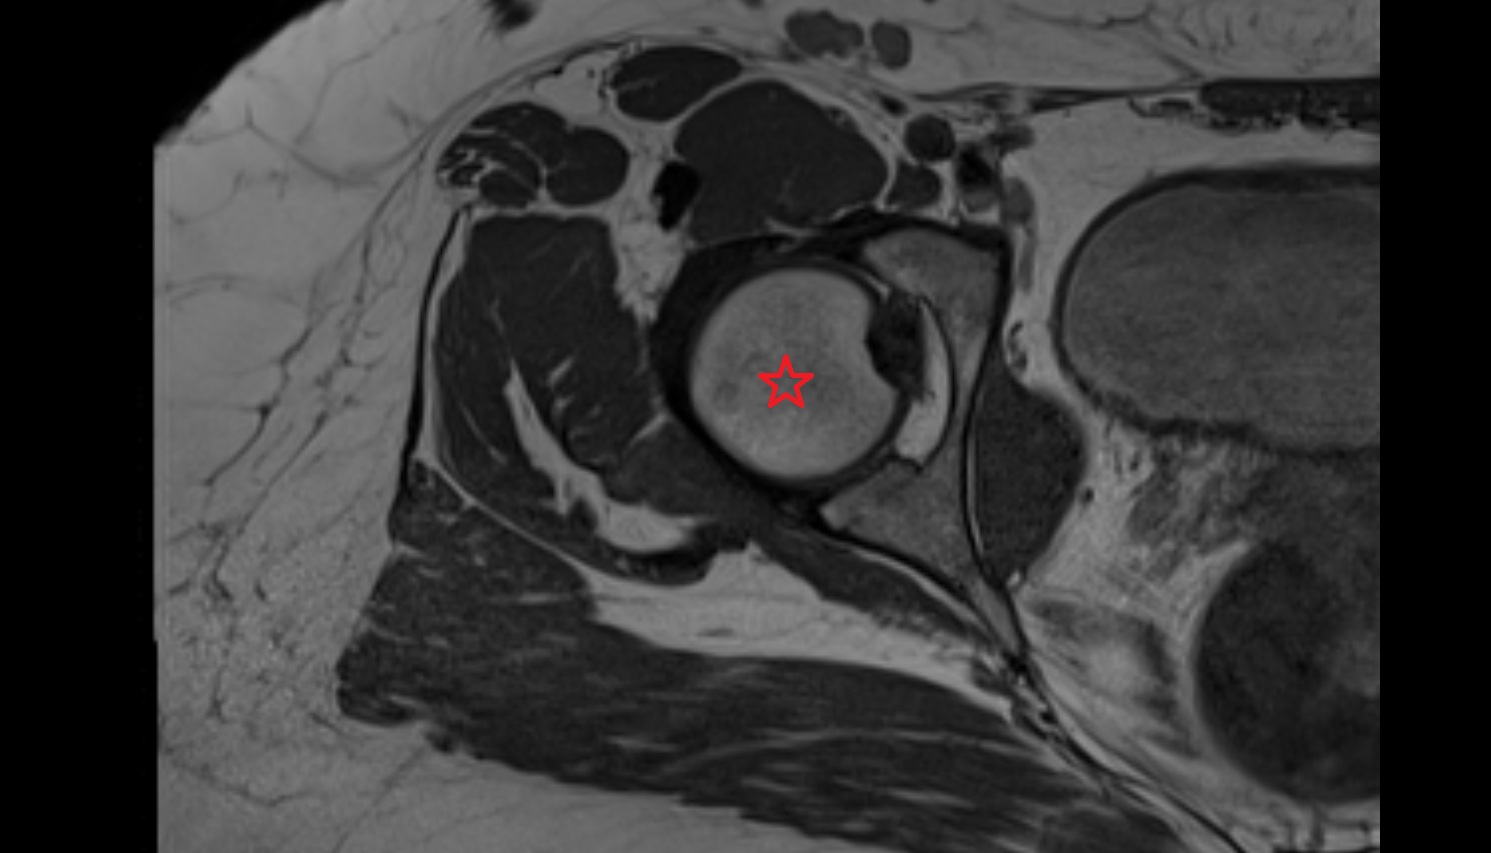

- Head of femur

- Hip joint